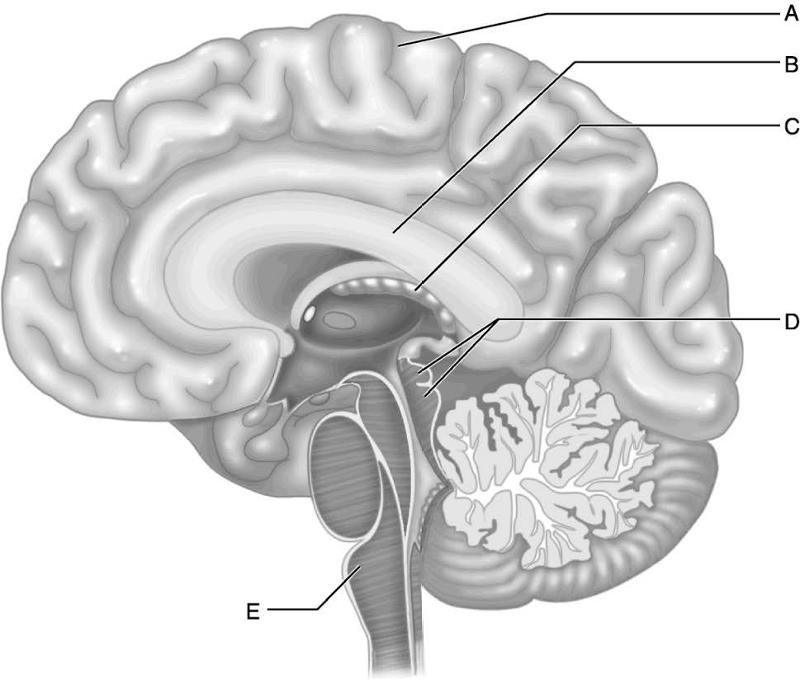

Which letter indicates the corpora quadrigemina, meaning "four

bodies?"

A) A

B) B

C) C

D) D

E) E

D

Which letter indicates the medulla, the functional neural connection

between the pons and the

spinal cord?

A) A

B) B

C)

C

D) D

E) E

E

Which letter indicates the region of the brain that has the greatest

surface area due to the

numerous surface convolutions?

A)

A

B) B

C) C

D) D

E) E

A

Which letter indicates a choroid plexus, which produces cerebrospinal

fluid (CSF)in all four

ventricles of the brain?

A) A

B)

B

C) C

D) D

E) E

C

Which letter indicates the corpus callosum, which is an area of white

matter where axons

from one cerebral hemisphere cross the midline

to the opposite hemisphere?

A) A

B) B

C) C

D)

D

E) E

B